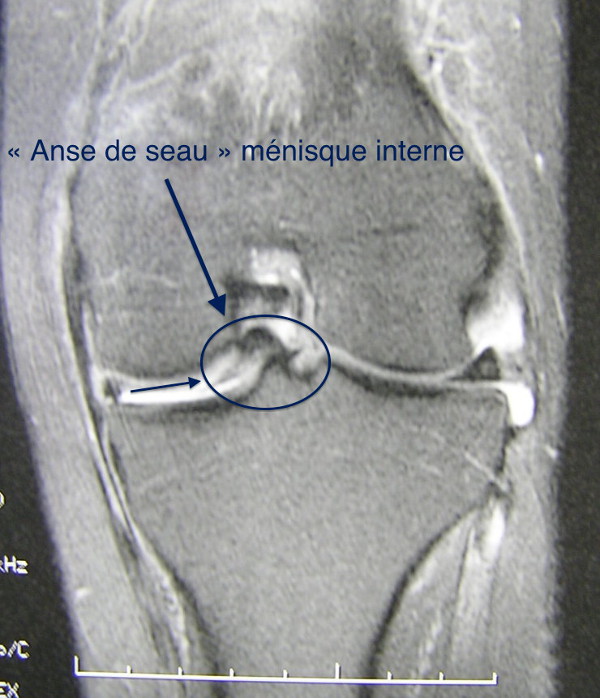

Chirurgie du Ménisque DR ANTOINE COMBES. Deux semaines après l opération j 'ai commencé les séances de kiné avec un total de 25 rendez vous. Ski: Réveille les douleurs si pratique intensive - j'en fait mais prudemment